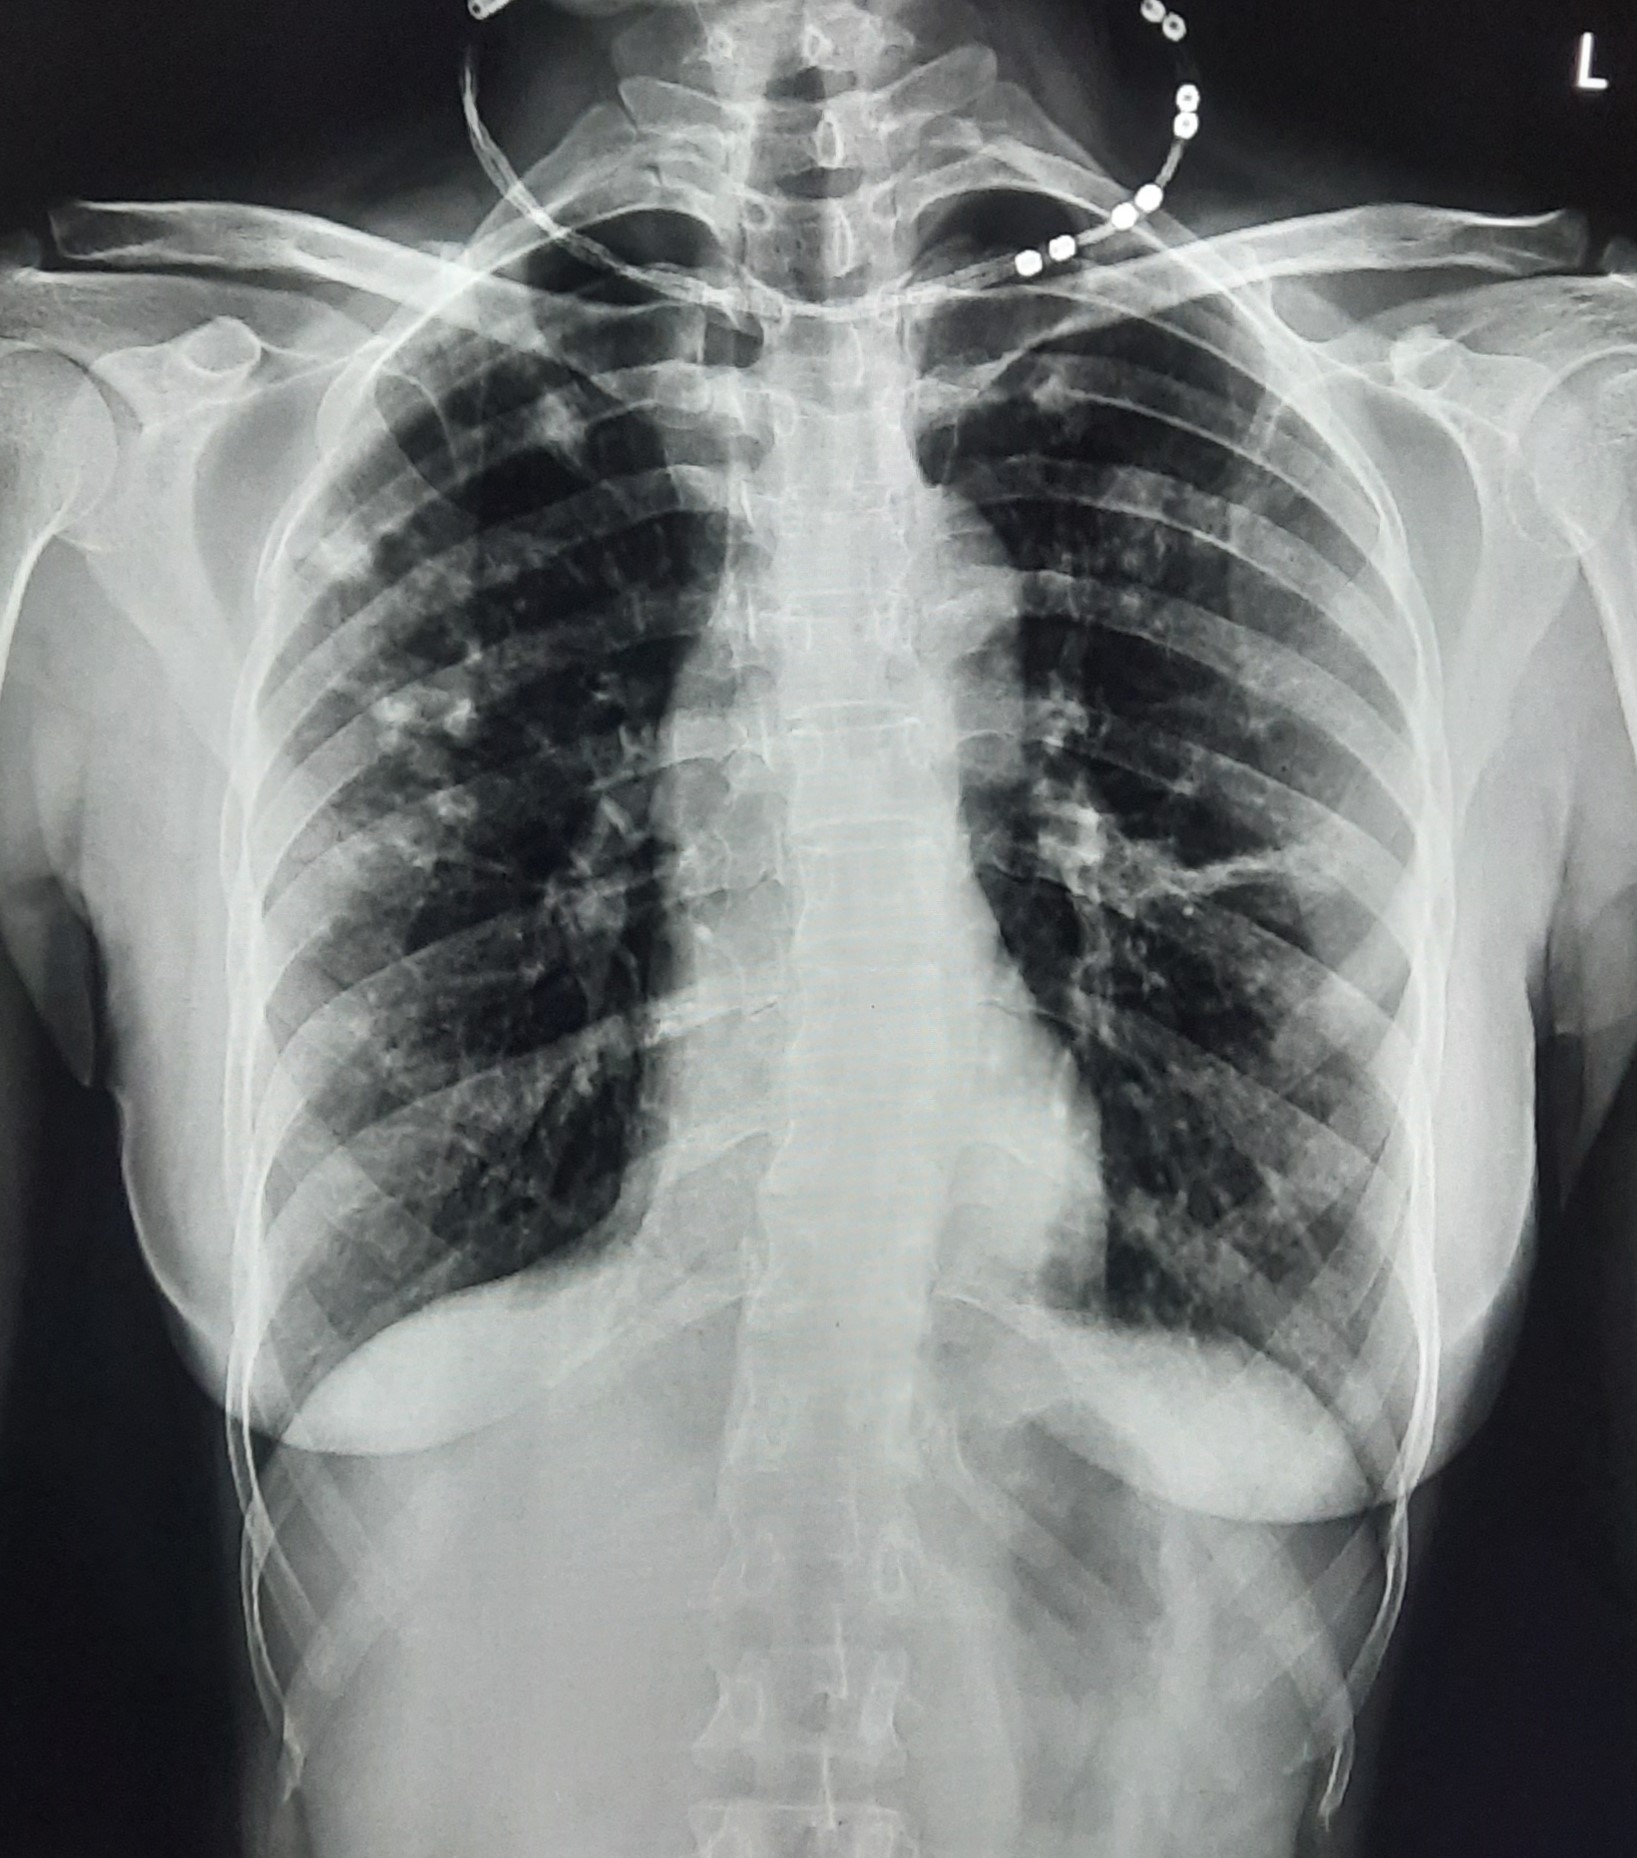

| 132 | IGGMC, Nagpur, Nagpur | P2 | 29-4340 | Ritesh Chaudhary | Consent taken on Paper | 30 Yrs. |

Provisional Diag : Post TB Sequelae

Final Diag : Post TB sequalae With Fibro Cavitary Changes |

Post TB Sequelae | Bilateral Upper Zone Fibro Cavitary Changes With Right Upper Zone Fungal Ball With Bilateral Haziness With Tenting Of Diaphragm | Abnormality visible on x-ray |